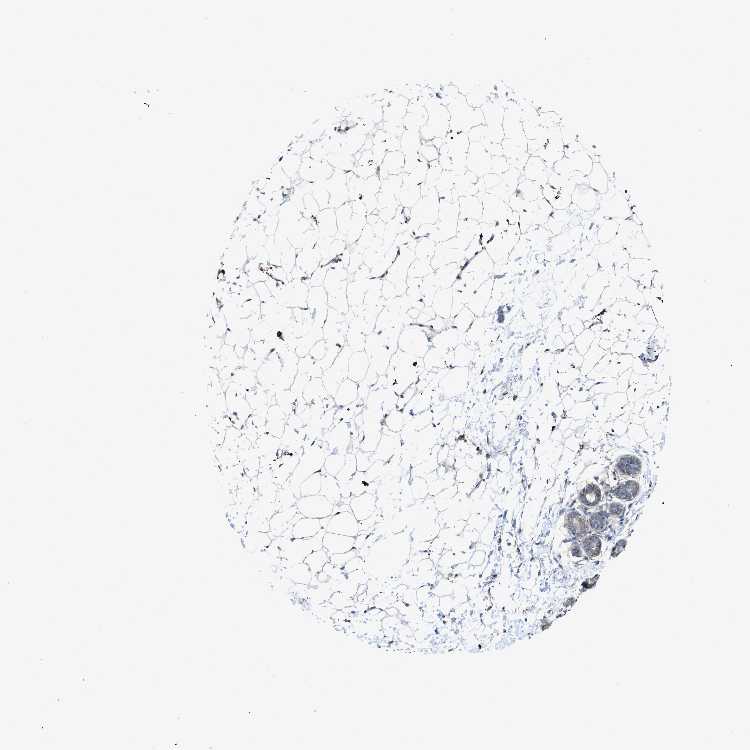

BREAST - Antibody stainingi

Antibody staining in the annotated cell types in the current human tissue is reported as not detected, low, medium, or high, based on conventional immunohistochemistry profiling in selected tissues. This score is based on the combination of the staining intensity and fraction of stained cells.

Each image is clickable and will lead to virtual microscopy that enables deeper exploration of all samples and also displays staining intensity scores, fraction scores and subcellular localization as well as patient and tissue information for each sample.

Antibody HPA001200Antibody HPA018530Antibody CAB000035Antibody CAB068186Antibody CAB073534Antibody CAB080313Antibody CAB080314Antibody CAB080473Antibody CAB080475Antibody CAB080506Antibody CAB080507Antibody CAB080509Antibody CAB080510Antibody CAB080511

Adipocytes Not detectedNot detectedLowNot detectedNot detectedHighMediumLowNot detected-HighNot detectedNot detected-

Glandular cells Not detectedMediumLowNot detectedLowHighNot detectedMediumMediumLowHighLowNot detectedNot detected

Myoepithelial cells Not detectedLowMediumNot detectedNot detectedNot detectedNot detectedMediumNot detectedNot detectedHighNot detectedNot detectedNot detected